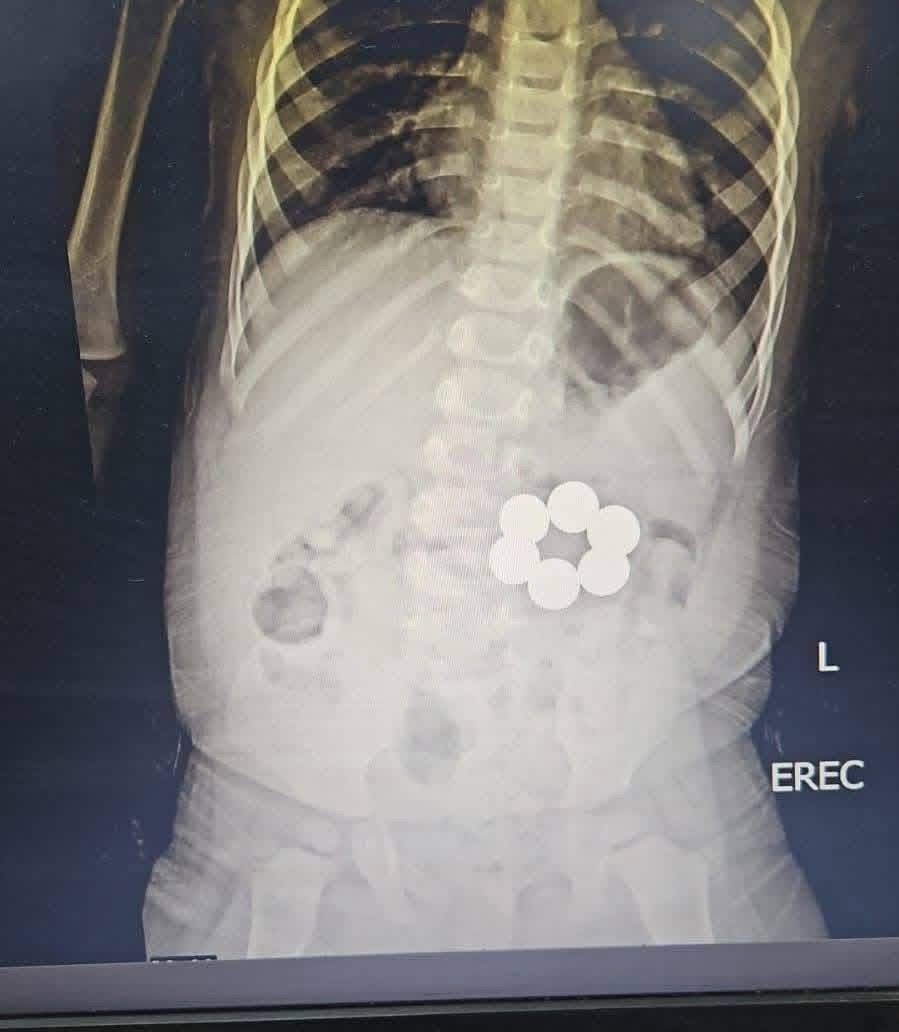

شهدت وحدة الجهاز الهضمي بمستشفى الأطفال الجامعي بالمنصورة نجاحًا طبيًا جديدًا، بعد تمكن فريق طبي متخصص من إنقاذ طفل رضيع يبلغ من العمر عامًا و4 أشهر، إثر ابتلاعه 6 قطع مغناطيس ذات قوة جذب عالية، في واقعة خطيرة كادت أن تهدد حياته.

وبحسب التفاصيل، خضعت حالة الطفل لتقييم إكلينيكي دقيق شمل مراجعة شاملة للفحوصات الطبية، قبل اتخاذ قرار التدخل العاجل باستخدام المنظار، حيث جرى تجهيز وحدة المناظير على أعلى مستوى لإجراء العملية بأمان.

ونجح الفريق الطبي في استخراج جميع القطع المغناطيسية بدقة عالية خلال وقت قياسي، دون تسجيل أي مضاعفات أثناء أو بعد الإجراء، مع الحفاظ الكامل على سلامة الجهاز الهضمي للطفل.